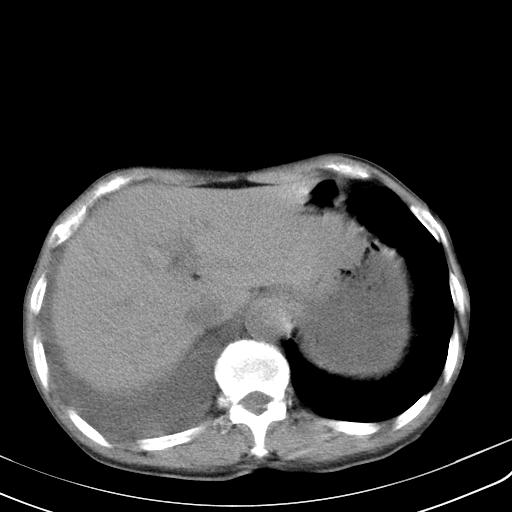

男性 75  咳嗽 一周前发热最高达39

右肺继发型tb并右侧tb性胸腔炎,右侧胸腔大量积液并右下肺膨胀不全,慢支肺气肿、多发肺大泡。建议抽胸水实验室检查并复查排除恶性在占位。

右上肺继发型肺结核,右胸腔中等量积液。

结核的基础上有纵隔淋巴结肿大,右侧有胸水,但右侧纵隔反而窄,说明有肺有不张。

再就是右下肺有块影,和不张混合,还是不能除外肺癌。

补充材料,患者2月份ct片大致正常,双侧胸腔积液,2月份抽胸水未发现ca细胞,现患者发热,痰多,各气管通畅,

1)右肺继发型肺结核。2)左肺胸膜下多发性肺大泡。3)右侧胸腔积液。